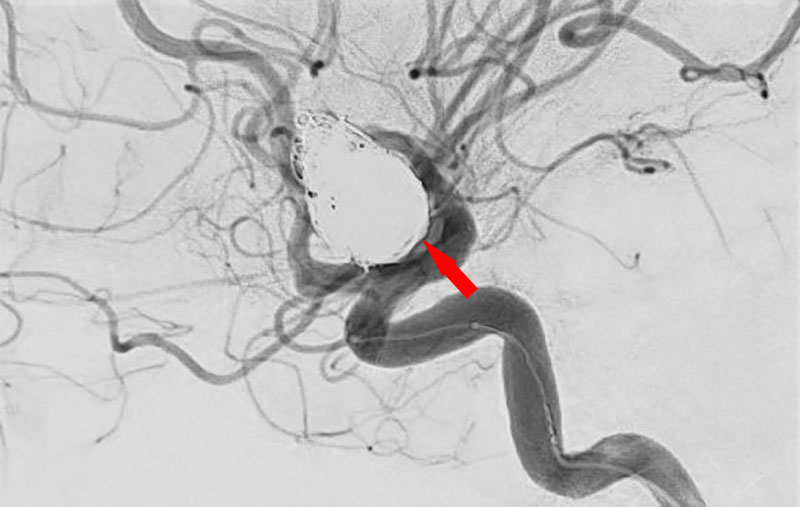

No.1628 手術後